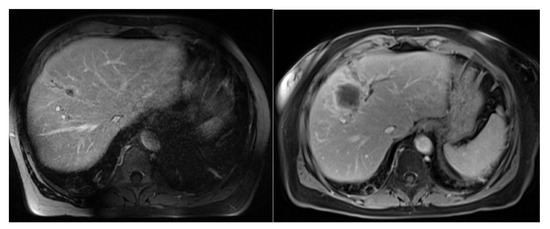

Stereotactic MR-Guided Radiotherapy for Liver Metastases: First Results of the Montpellier Prospective Registry Study

by Karl Bordeau, Morgan Michalet, Aïcha Keskes, Simon Valdenaire, Pierre Debuire, Marie Cantaloube, Morgane Cabaillé, William Jacot, Roxana Draghici, Sylvain Demontoy, Xavier Quantin, Marc Ychou, Eric Assenat, Thibault Mazard, Ludovic Gauthier, Marie Dupuy, Boris Guiu, Céline Bourgier, Norbert Aillères, Pascal Fenoglietto, David Azria and Olivier Riouadd Show full author list remove Hide full author list

J. Clin. Med. 2023, 12(3), 1183; https://doi.org/10.3390/jcm12031183 - 2 Feb 2023

Liver stereotactic body radiotherapy (SBRT) is a local treatment that provides good local control and low toxicity. We present the first clinical results from our prospective registry of stereotactic MR-guided radiotherapy (MRgRT) for liver metastases. All patients treated for liver metastases were included [...] Read more.

Liver stereotactic body radiotherapy (SBRT) is a local treatment that provides good local control and low toxicity. We present the first clinical results from our prospective registry of stereotactic MR-guided radiotherapy (MRgRT) for liver metastases. All patients treated for liver metastases were included in this prospective registry study. Stereotactic MRgRT indication was confirmed by multidisciplinary specialized tumor boards. The primary endpoints were acute and late toxicities. The secondary endpoints were survival outcomes (local control, overall survival (OS), disease-free survival, intrahepatic relapse-free survival). Twenty-six consecutive patients were treated for thirty-one liver metastases between October 2019 and April 2022. The median prescribed dose was 50 Gy (40–60) in 5 fractions. No severe acute MRgRT-related toxicity was noted. Acute and late gastrointestinal and liver toxicities were low and mostly unrelated to MRgRT. Only 5 lesions (16.1%) required daily adaptation because of the proximity of organs at risk (OAR). With a median follow-up time of 17.3 months since MRgRT completion, the median OS, 1-year OS and 2-year OS rates were 21.7 months, 83.1% (95% CI: 55.3–94.4%) and 41.6% (95% CI: 13.5–68.1%), respectively, from MRgRT completion. The local control at 6 months, 1 year and 2 years was 90.9% (95% CI: 68.3–97.7%). To our knowledge, we report the largest series of stereotactic MRgRT for liver metastases. The treatment was well-tolerated and achieved a high LC rate. Distant relapse remains a challenge in this population. Full article